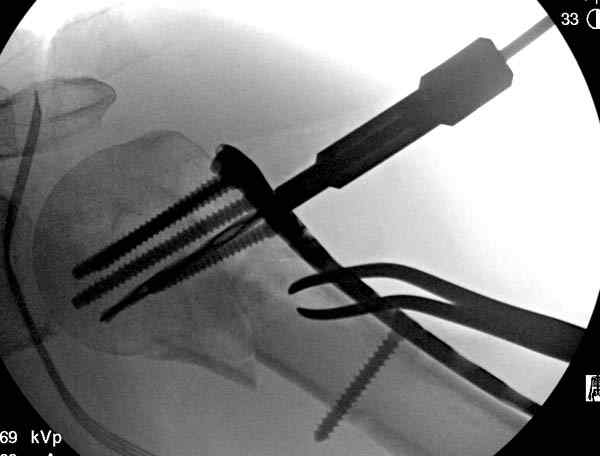

Здесь пример открытой репозиции 57 летнего с переломом плеча (1,2) смещение обнаружено на интероперационном снимке. При нормальной прямой проекция (3) угловое смещение обнаружили в аксиальной проекции (4)